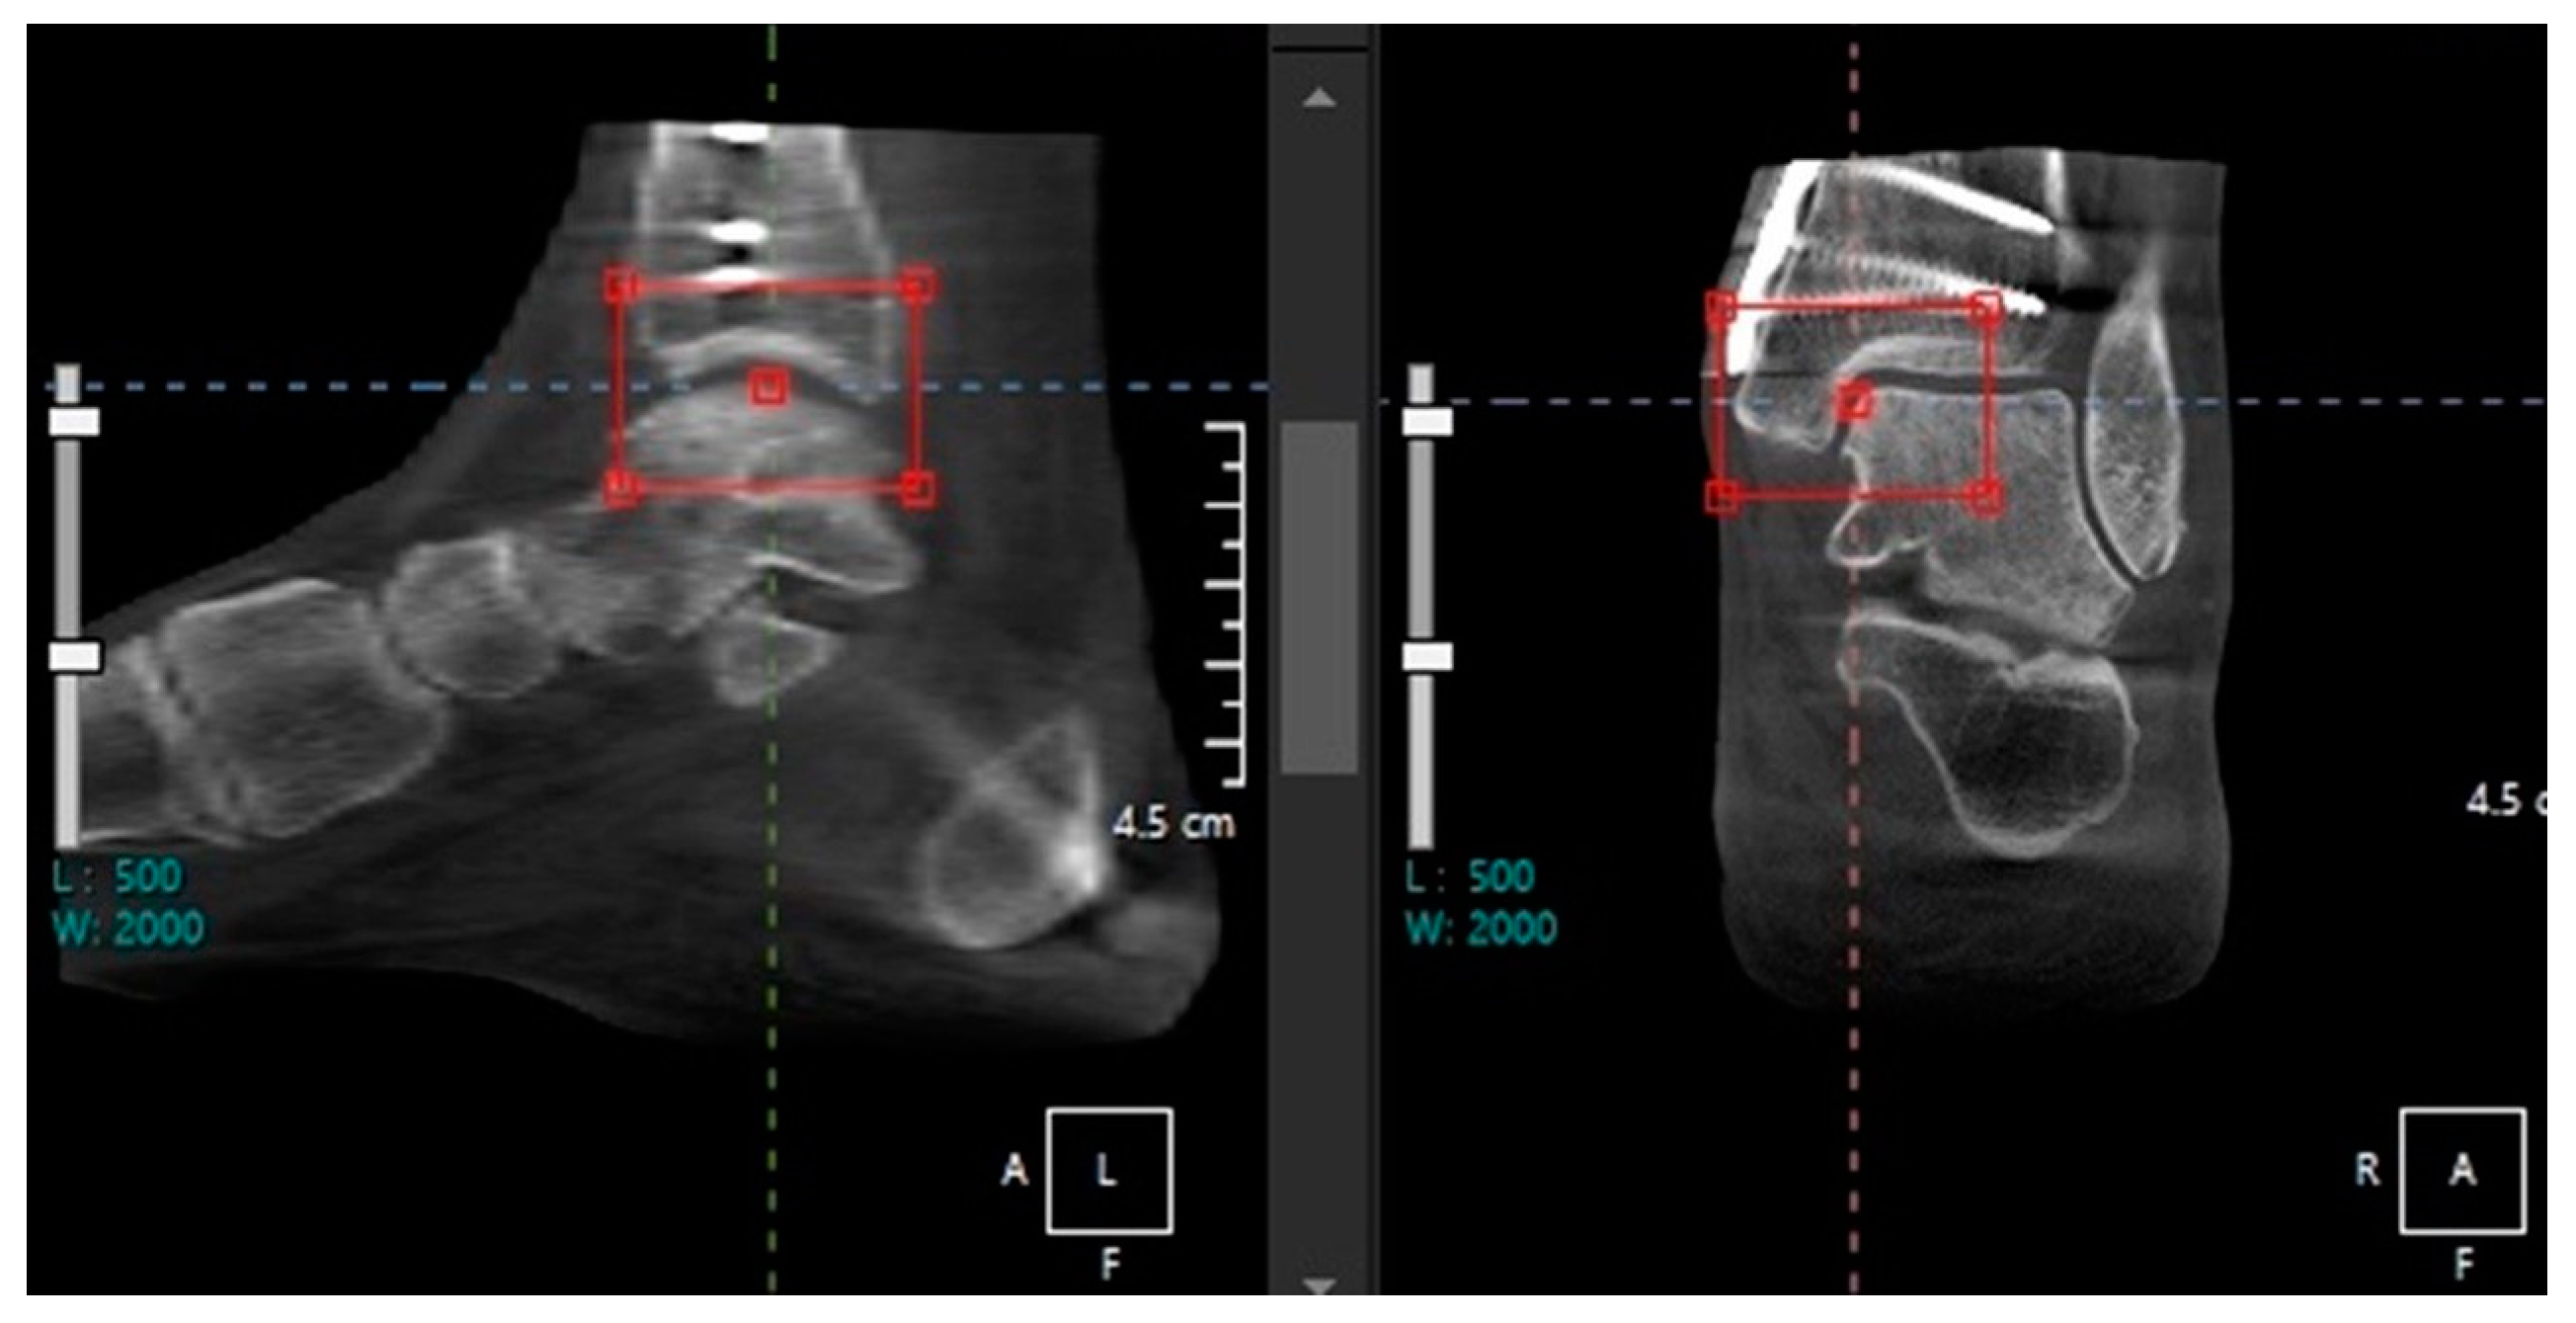

- Tazegul, T.E.; Anderson, D.D.; Barbachan Mansur, N.S.; Kajimura Chinelati, R.M.; Iehl, C.; VandeLune, C.; Ahrenholz, S.; Lalevee, M.; de Cesar Netto, C. An Objective Computational Method to Quantify Ankle Osteoarthritis from Low-Dose Weightbearing Computed Tomography. Foot Ankle Orthop. 2022, 7, 24730114221116805. [Google Scholar] [CrossRef]